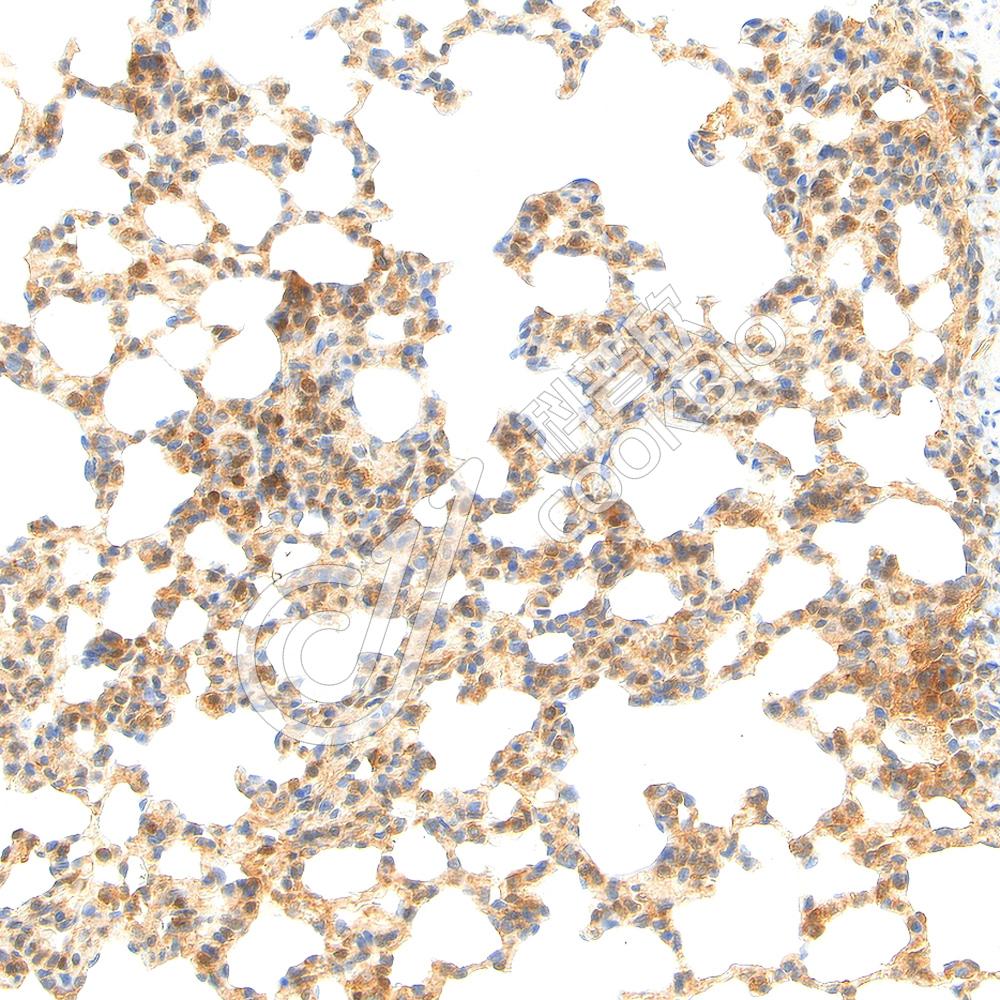

IHC检测GSDMD蛋白(货号 K5462594).

样品: 大鼠lps(6h)诱导的肺部炎症模型, 4%多聚甲醛 (货号KSG1101) 固定12-24小时.

抗原修复: Tris-EDTA抗原修复液(pH 9.0) (KSG1203), 98℃, 20分钟.

—抗: 1: 1500稀释, 4℃ 孵育过夜.

二抗: S-vision免疫组化多聚二抗(山羊抗兔),即用型 (货号KB3906), 室温孵育20分钟.